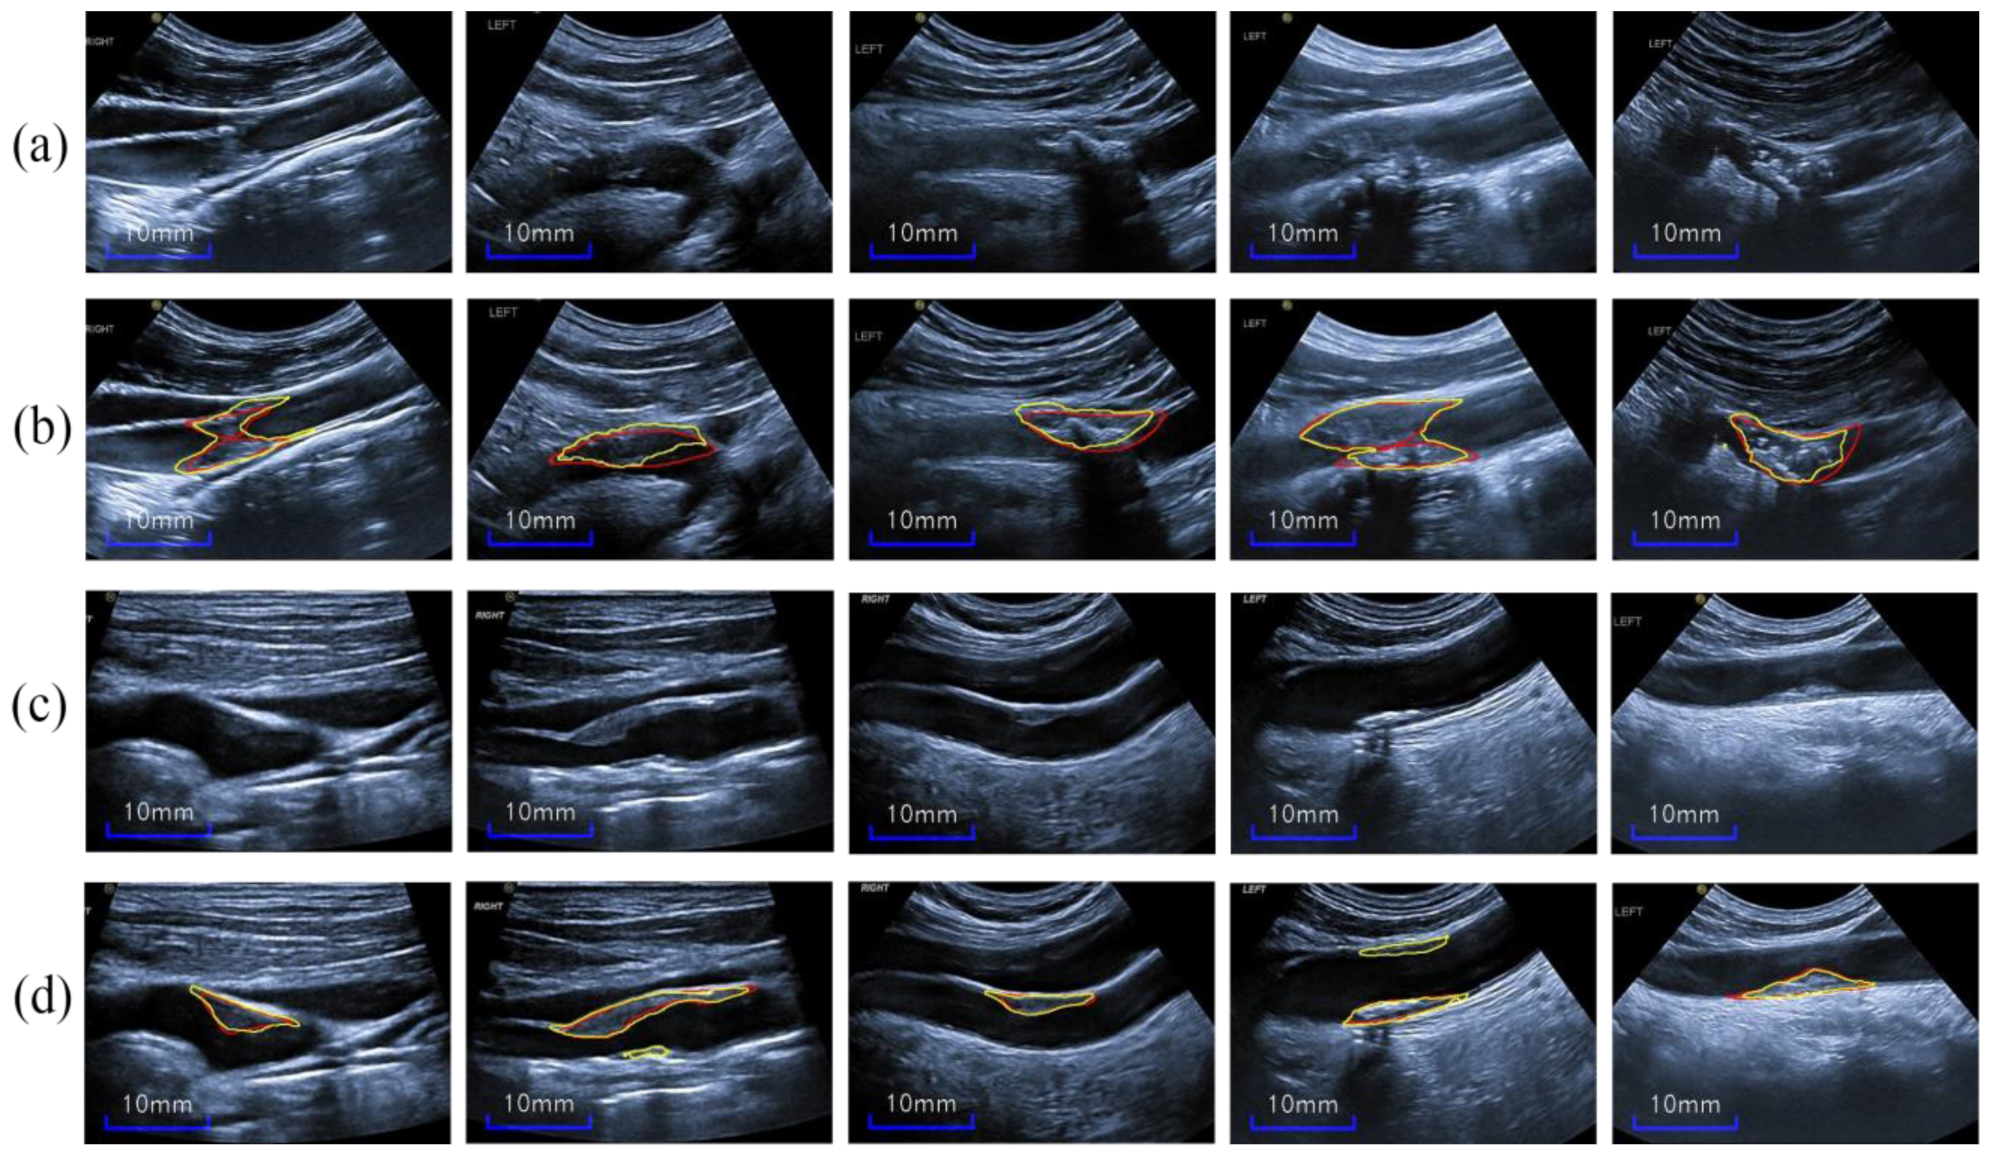

4.3. Test Results on New Images